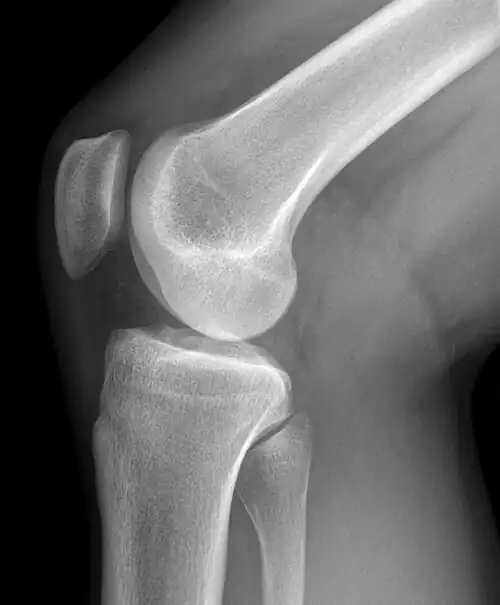

Se llama articulación de la rodilla a la articulación central de los miembros posteriores o inferiores de los vertebrados, en el caso de la especie humana es la articulación central de los miembros inferiores.[1] La rodilla está formada principalmente por la unión de 2 huesos, el fémur en su porción distal, y la tibia en la porción proximal. Dispone asimismo de un pequeño hueso, llamado rótula, que se articula con la porción anterior e inferior del fémur. Puede realizar principalmente movimientos de flexión y extensión. Está rodeada por una cápsula articular y varios ligamentos que le dan estabilidad. En sus proximidades se insertan potentes músculos que hacen posible el movimiento de la extremidad.

Aspectos generales

En el ser humano, la articulación de la rodilla es la articulación más grande del cuerpo y una de las más complejas. Sirve de unión entre el muslo y la pierna. Soporta la mayor parte del peso del cuerpo en posición de pie. Está compuesta por la acción conjunta de los huesos fémur, tibia, rótula y dos discos fibrocartilaginosos que son los meniscos. Fémur y tibia conforman el cuerpo principal de la articulación, mientras que la rótula actúa como una polea y sirve de inserción al tendón del músculo cuadriceps y al tendón rotuliano cuya función es transmitir la fuerza generada cuando se contrae el cuádriceps.[2][3]

Elementos óseos

El extremo inferior del fémur presenta dos protuberancias redondeados llamadas cóndilos que están separadas por un espacio intermedio que se denomina espacio intercondileo.

Por su parte el extremo superior de la tibia posee dos cavidades, las cavidades glenoideas, que sirven para albergar a los cóndilos del fémur. Entre las dos cavidades glenoideas se encuentran unas prominencias, las espinas tibiales, en las que se insertan los ligamentos cruzados. En la parte anterior de la tibia existe otro saliente, la tuberosidad anterior que sirve de inserción al tendón rotuliano.

Por otra parte la rótula se articula en su porción posterior con una parte del fémur que se llama tróclea femoral. Entre ambas superficies se interpone un cartílago, el cartílago prerrotuliano que amortigua la presión entre los dos huesos.[7]